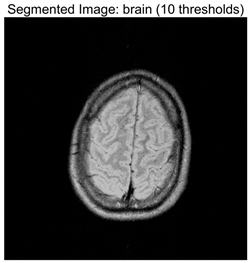

Table 8 presents the distributions of the optimal thresholds selected by each algorithm on the image histograms. Table 9 reports the mean and standard deviation of the best fitness values obtained by each algorithm based on the Otsu objective function, along with their average performance rankings. Furthermore, Table 10, Table 11 and Table 12 summarize the mean, standard deviation, and average ranking of each algorithm in terms of PSNR, FSIM, and SSIM, respectively. The experiments cover four threshold levels (4, 6, 8, and 10), with all results obtained through optimal threshold search using the Otsu criterion.

Table 9 focuses on the optimal fitness values obtained based on the Otsu objective function (maximization of inter-class variance), which directly reflects the algorithms’ ability to search for segmentation thresholds. Higher Ave values indicate that the thresholds are closer to the global optimum, while lower Std values reflect greater consistency across multiple runs. From the data distribution, RLTC-SCA exhibits a dual advantage of “high Ave + low Std” across all image and threshold-level combinations. For instance, in the brain image (a medical brain image with complex grayscale distribution), when TH = 4, RLTC-SCA achieves an Ave value of 3.7306 × 103, comparable to AGPSO and MVO, but its Std value (2.3126 × 10−12) is only 1.53 × 10−11 times that of AGWO (1.5156 × 10−1), showing virtually no fluctuation. At TH = 10, its Ave value (3.7694 × 103) still surpasses standard SCA (3.7644 × 103) and AGWO (3.7691 × 103), with a Std value (1.3312 × 10−1) amounting to merely 3.81% of IVYA (3.4907 × 100), demonstrating stable threshold-search accuracy even at high threshold levels. In the camera image (industrial scene image with low grayscale contrast), at TH = 4, RLTC-SCA’s Ave value (4.6008 × 103) is 0.01% higher than the second-best AGPSO (4.6003 × 103), while its Std value (0.69397) is only 39.44% of standard SCA (1.7594), validating that the reinforcement learning-based action selection strategy can dynamically adjust search actions to avoid threshold selection bias in smooth grayscale distributions. In contrast, algorithms such as IVYA, lacking guided global exploration, show lower Ave values and Std values exceeding 3.0 × 100 in most images, ranking last (8th) in the Friedman ranking, compared with RLTC-SCA ranked 1st.